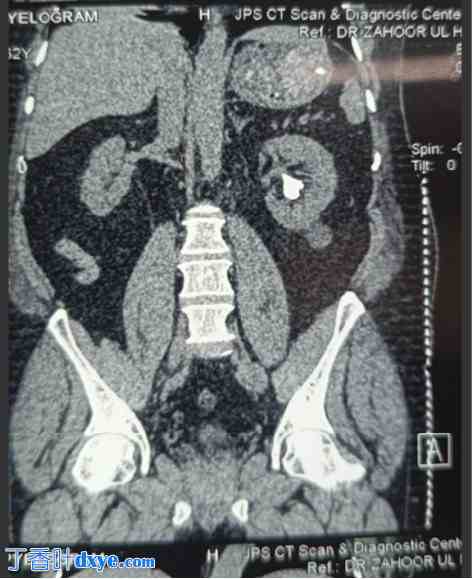

图2

CT扫描显示左肾静脉内有肾造瘘管。

患者插入肾造瘘管5小时后出现剧烈出血,随后导致低血压。患者被转至重症监护病房 (HDU) 进行复苏治疗。输注4单位血液和新鲜冰冻血浆 (FFP),患者的血流动力学得以稳定。进一步的放射影像学检查,特别是CT血管造影,显示肾造瘘管意外穿过左肾下极肾盏,到达左肾静脉,其尖端距离下腔静脉 (IVC) 开口仅2毫米(图5)。通过液体复苏和夹紧PCN管,患者病情得以稳定。